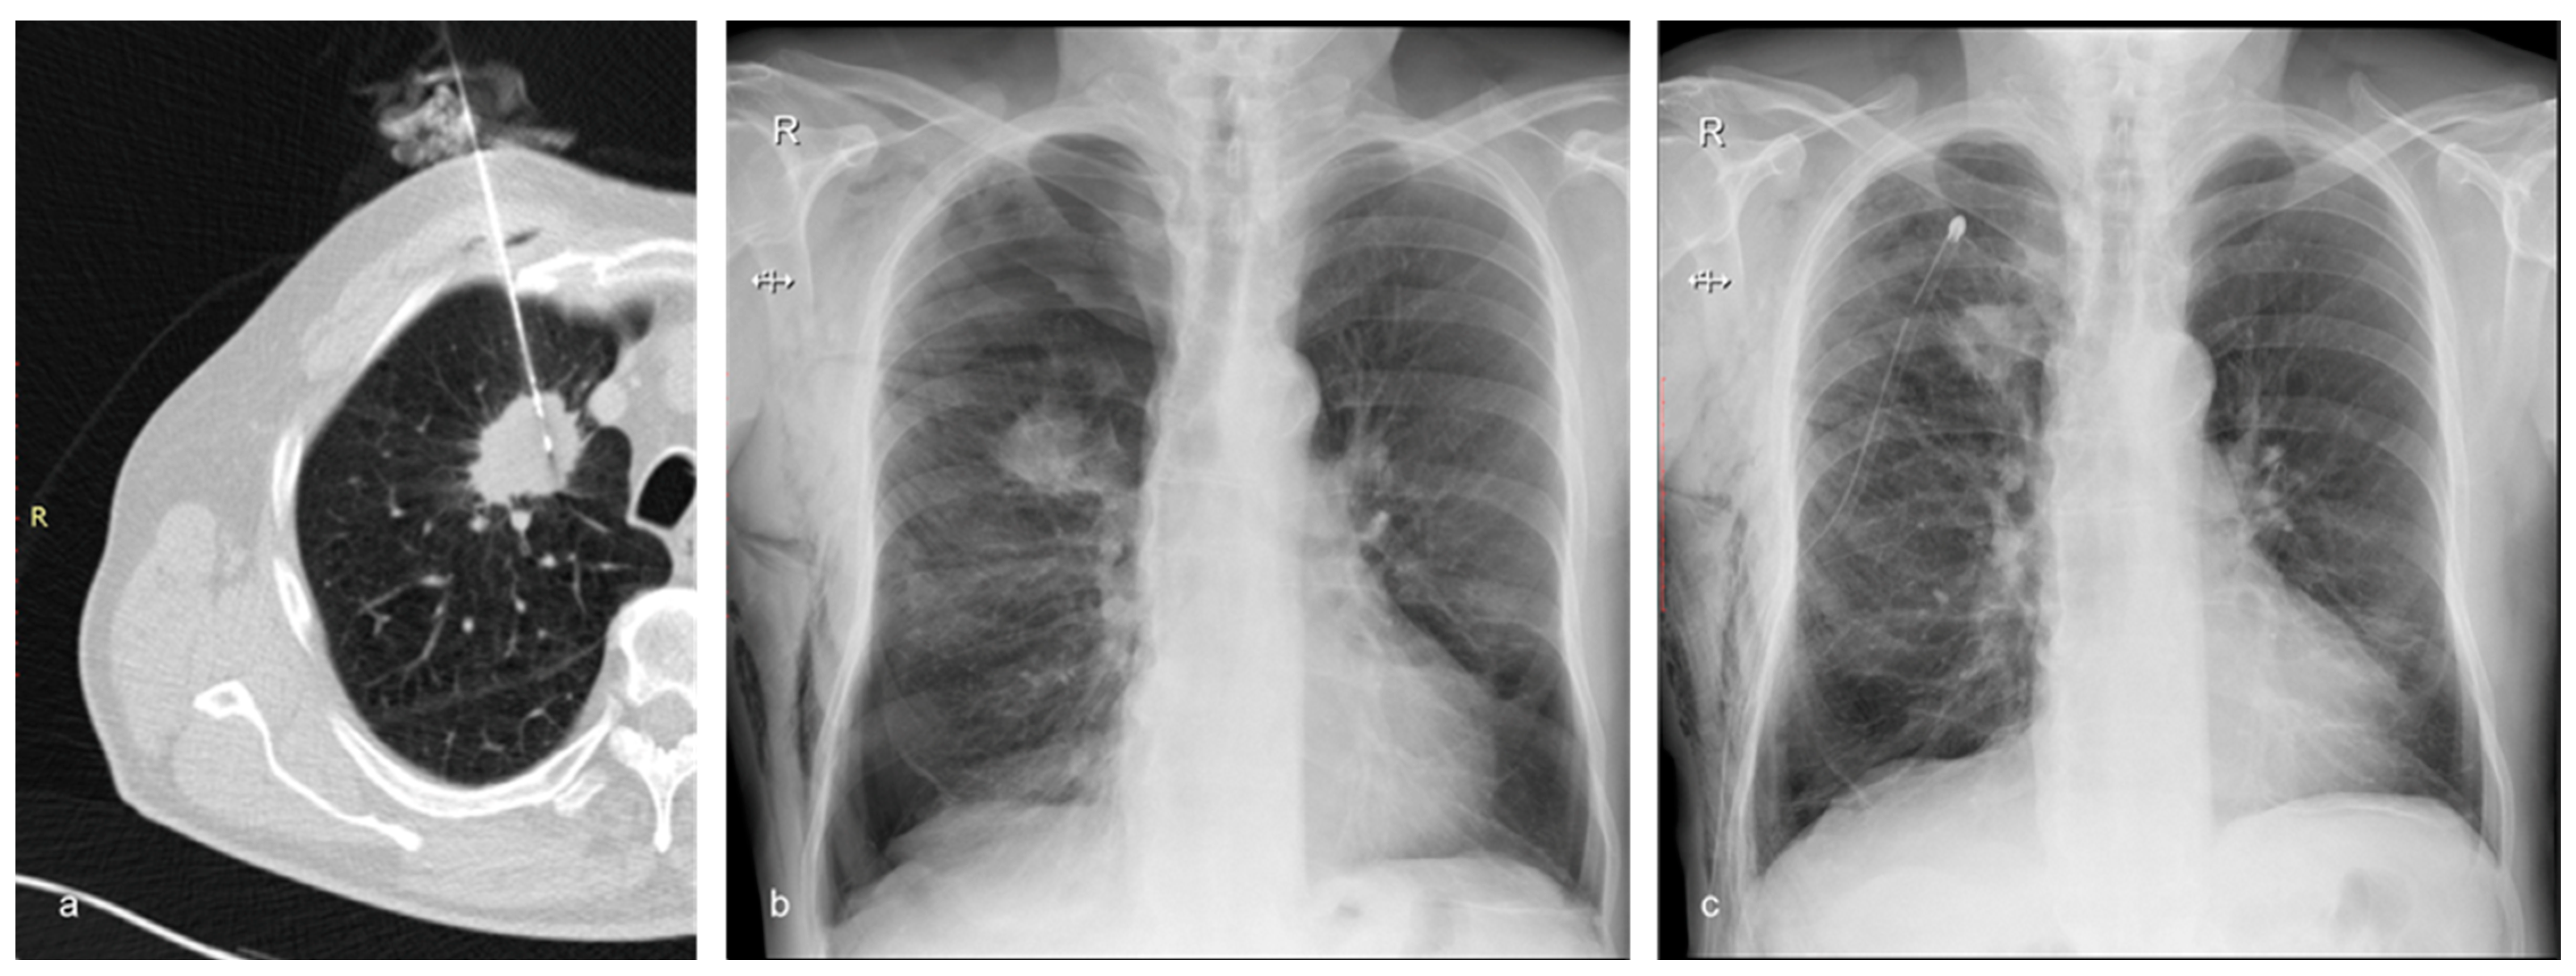

Figure 3.

A 72-year-old man with emphysema and a tumor in the right upper lobe belonging to Group B (the treatment group). The nodule was confirmed to be adenocarcinoma by the histopathological examination. (a) Axial CT showing the 17G coaxial needle and the 18G biopsy needle within the lung mass. (b) Chest X-ray performed 2 h after the biopsy showing moderate post-procedural pneumothorax and subcutaneous emphysema. The patient complained of right chest pain and dyspnea. It was decided to insert a chest tube to prevent further expansion of the pneumothorax and to alleviate the symptoms. (c) Chest X-ray of the same patient following the insertion of the chest drain.